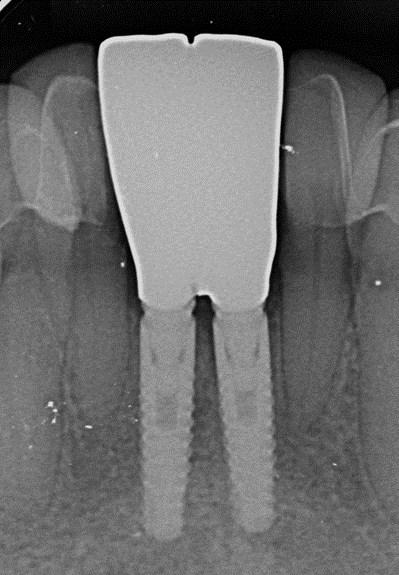

Do ponto de vista protético, havia um fator crítico a ser considerado: o espaço mésio-distal reduzido na região dos incisivos inferiores. Frequentemente, o espaço entre raízes de incisivos inferiores ou entre um canino e a linha média é inferior a 6 mm, tornando inviável a instalação de implantes convencionais (>3,5 mm) sem risco de invadir o espaço periodontal dos dentes vizinhos. Nesse contexto, implantes de diâmetro reduzido são indicados para reabilitar áreas com disponibilidade óssea limitada, como incisivos laterais superiores ou incisivos inferiores. Optou-se pelo implante Stretto (Implacil Osstem) de 3,0 mm de diâmetro e 11,5 mm de comprimento exatamente por essa limitação de espaço. Essa linha de implantes, por possuir conexão interna cônica do tipo cone morse indexado, maximiza a área de contato osso-implante e a estabilidade do pilar protético mesmo em diâmetros estreitos. Vale destacar que estudos relatam que a redução do diâmetro do implante, quando compensada por comprimento adequado e por um desenho de conexão interna, não prejudica as taxas de sucesso ou a perda óssea marginal em comparação a implantes de diâmetro padrão. Em suma, o planejamento considerou a necessidade de preservar os tecidos, a escolha de um implante compatível com o espaço anatômico disponível e a preparação de medidas para manutenção do volume alveolar pós-extração.

Em um primeiro momento foi feito um pequeno desgaste com ponta diamantada nas faces mesiais dos dentes 32 e 42 para aumentar o espaço mésio-distal. Com a paciente sob anestesia local adequada, procedeu-se às exodontias dos incisivos 31 e 41 utilizando técnica minimamente traumática. Realizou-se incisão intrasulcular ao redor dos dentes e uso delicado de periótomo e alavancas de pequeno porte, promovendo a luxação e remoção cuidadosa das raízes sem descolar retalhos mucoperiostais. Essa técnica conservadora preservou os tecidos peri-implantares – em especial a papila interdental entre os dentes 32 e 42 – e manteve a integridade das paredes ósseas alveolares, fundamentais para a estética e cicatrização. Confirmada a ausência de fenestrações ou deiscências ósseas pós-exodontia, prosseguiu-se imediatamente com a osteotomia para instalação dos implantes. Seguiu-se o protocolo de fresagem recomendado pelo fabricante para o implante Stretto, utilizando sequência de brocas de diâmetro incremental adequado à densidade óssea presente. O conjunto Stretto apresenta brocas desenhadas para preparos precisos e minimamente invasivos, facilitando a instalação em sítios com espaço limitado. A preparação atingiu estabilidade primária suficiente apicalmente, permitindo o travamento dos implantes nos alvéolos frescos. Foram instalados dois implantes cone morse Stretto (Ø 3,0 mm x 11,5 mm) nas posições 31 e 41, posicionados de forma centralizada nos respectivos alvéolos e com paralelismo adequado entre si. Importante notar que o implante Stretto foi desenvolvido especificamente para situações críticas de espaço protético e ósseo reduzido, combinando facilidade cirúrgica e versatilidade protética para reabilitar tais casos.

Para os implantes, foram selecionados pilares protéticos retos da linha Stretto compatíveis com a plataforma reduzida dos implantes utilizados (diâmetro aproximado de 3,5 mm). Devido ao correto posicionamento tridimensional dos implantes, não houve necessidade de pilares angulados, simplificando a reabilitação. Esses pilares retos foram instalados e avaliados clinicamente (prova dos pilares), apresentando excelente adaptação e estabilidade. Com os pilares definitivos posicionados e aprovados, prosseguiu-se para a etapa de confecção das restaurações finais sobre implante.